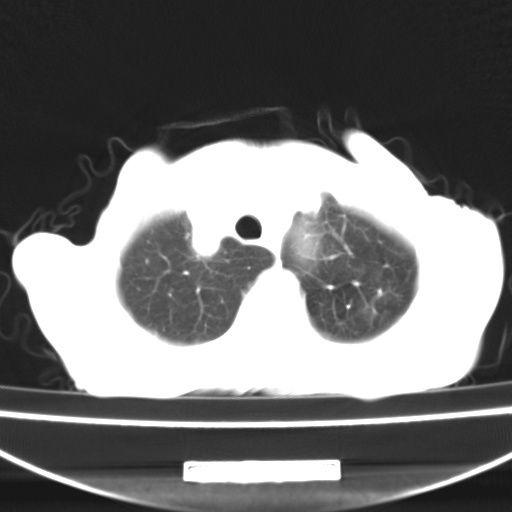

患者 女 67岁,反复咳嗽咳痰2年,加重伴喘及双下肢浮肿1月

诸大血管及f肺门血管增粗迂曲.左下肺多发薄壁空腔影.部分非也透亮度增高.薄曾扫描可区分肺气肿类型.考虑1.慢性支气管炎 2.左下肺支气管扩张 3.肺气肿 4 肺动脉高压5.是否有先心病病史

考虑1.慢性支气管炎 2.左下肺支气管扩张 3.肺气肿 4 肺动脉高压

慢支炎、肺气肿、双肺感染、左下囊状支扩。

慢支、肺气肿、肺动脉高压;左下肺囊状支扩并粘液栓形成。